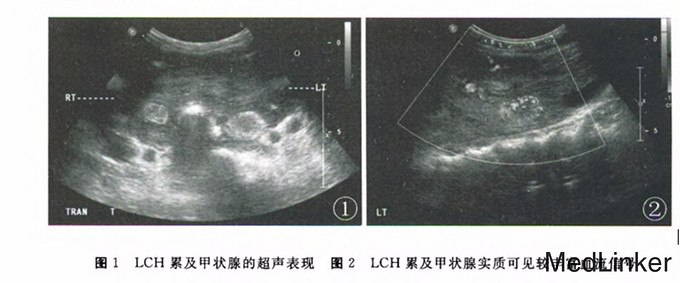

查体::颈部对称,未见颈静脉怒张及颈动脉异常搏动,颈部无抵抗,颈部可触及5cm×6cm大小肿物,质韧,边界清晰,无触痛,表面光滑,随吞咽上下移动,颈部未闻及明显血管杂音。 辅查:超声检查所见:甲状腺体积增大,被膜凹凸不平,似呈浸润性生长,与周围组织界限不清。实质回声不均匀,并可见数个中强回声结节,左侧叶其中一个大小约2.22cm*1.63cm,右侧叶其中一个大小约1.43cm*1.08cm,上述结节边界欠清,形态尚规整。CDFI显示甲状腺实质血流信号较丰富

朗格汉斯细胞正常存在于皮肤和黏膜的基底层上皮细胞,属于组织细胞系统。格汉斯细胞组织细胞增生症呈单灶或弥漫状,全身器官皆可受累。最常见侵犯部位为骨,皮肤、淋巴结、肺、肝、脾、内分泌腺及神经系统。。本例朗格汉斯细胞组织细胞增生症患者在诊疗过程中发现除累及甲状腺外,鞍上漏斗部及视交叉区也受侵。其在甲状腺超声声像图表现方面与其他甲状腺实质弥漫性病变伴发结节相比无明显特异性表现,无法明确诊断,但较CT及ECT能清楚了解其与周围组织的关系及它的生长方式,朗格汉斯细胞组织细胞增生症的定性诊断仍需依赖病理检查。